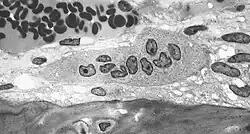

Osteoclast

Osteoclastele sunt celule implicate în distrugerea țesutului osos. Această funcție este critică în procesele de menținere, reparare și remodelare a osului în scheletul vertebratelor. Osteoclastele dezasamblează și digeră compoziția proteinelor hidratate și a mineralelor ca urmare a secreției de acid și colagenază, proces cunoscut sub numele de resorbție osoasă. Acest proces este implicat și în reglarea nivelelor de calciu din sânge.[1]